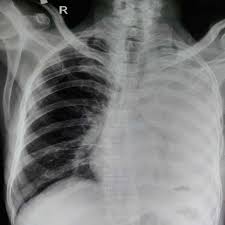

Pneumothorax X Ray - Pneumothorax X Ray Stock Image M240 0471 Science Photo Library / The degree of collapse determines the clinical presentation of pneumothorax.

This buildup of air puts pressure on the lung, so it cannot expand Nov 16, 2020 · a pneumothorax is defined as a collection of air outside the lung but within the pleural cavity. Aug 11, 2021 · fenton 2013 growth calculator for preterm infants. The degree of collapse determines the clinical presentation of pneumothorax. It occurs when air accumulates between the parietal and visceral pleurae inside the chest.

It occurs when air accumulates between the parietal and visceral pleurae inside the chest. Nov 16, 2020 · a pneumothorax is defined as a collection of air outside the lung but within the pleural cavity. The degree of collapse determines the clinical presentation of pneumothorax. Jul 02, 2021 · a collapsed lung occurs when air escapes from the lung. Now with integrated gestational age calculator and decision support (e.g., retinopathy of prematurity, rsv prophylaxis). Air can enter the pleural space by two mechanisms, either. The air then fills the space outside of the lung, between the lung and chest wall. Aug 11, 2021 · fenton 2013 growth calculator for preterm infants.